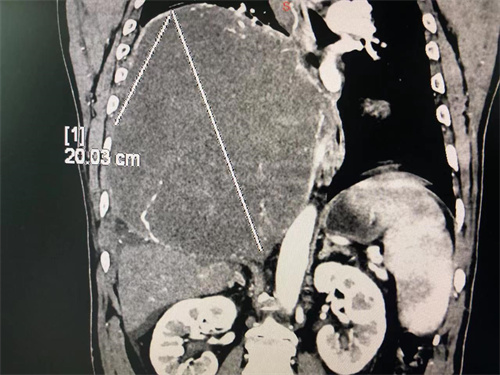

去年8月开始,刘大叔偶有咳嗽和少量白粘痰,稍稍活动就感胸闷不适,当时未引起重视;到了12月,因新冠病毒感染,引发剧烈咳嗽,且核酸结果转阴后咳嗽仍不见好转,身体也逐渐消瘦,前往南昌多家省级三甲医院就诊,行胸部CT提示右侧胸腔有一巨大软组织密影,直径约28厘米,病灶累及右侧膈肌,经皮肺穿刺活检,提示为“孤立性纤维肿瘤”。

1月8日,刘大叔第一次来到江西省肿瘤医院住院。完善相关检查,发现肿瘤不仅几乎占满整个右侧胸腔,且瘤体血供极其丰富并与周围组织器官形成侧支循环,同时向下压迫膈肌、肝脏,向左压迫心脏。虽有手术机会,但手术难度极大、风险极高。因刘大叔想春节一家人团圆,检查完成后便出院回家。

充分做好各项术前准备,2月9日,刘大叔在全麻下接受了“右侧胸腔巨大肿瘤切除术+右下肺部分切除术+右侧膈肌大部位切开修补术+肋骨离断重建术+胸膜黏连松解术”。胸部、腹部、肝胆肿瘤外科/介入科及医学影像、医学输血、麻醉科、病理科、重症医学科及手术室等学科医护人员全力以赴、密切协作,共同为刘大叔手术。手术历时近8小时,终于完整切除了直径约28cm、重约4千克的瘤体。